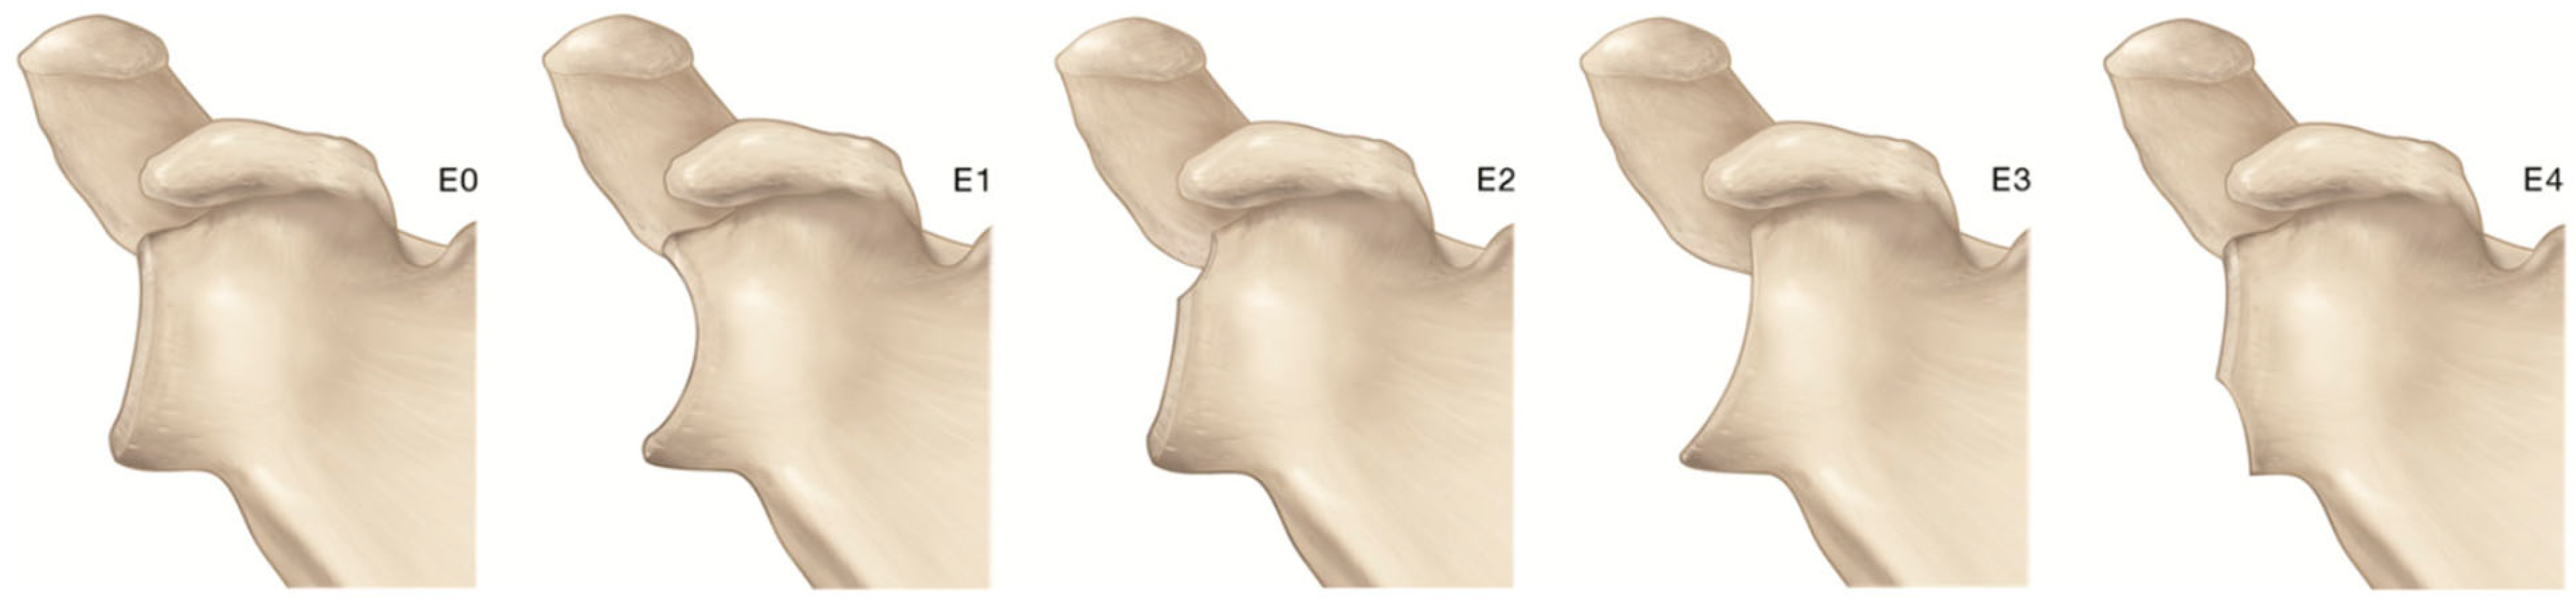

2. Gleno-Humeral Deformity in Primary Osteoarthritis and Cuff Tear Arthropathy

- Walch, G.; Badet, R.; Boulahia, A.; Khoury, A. Morphologic Study of the Glenoid in Primary Glenohumeral Osteoarthritis. J. Arthroplast. 1999, 14, 756–760. [Google Scholar] [CrossRef] [PubMed]

- Kidder, J.F.; Rouleau, D.M.; DeFranco, M.J.; Pons-Villanueva, J.; Dynamidis, S. Revisited: Walch Classification of the Glenoid in Glenohumeral Osteoarthritis. Shoulder Elb. 2012, 4, 11–15. [Google Scholar] [CrossRef]

- Bercik, M.J.; Kruse, K.; Yalizis, M.; Gauci, M.-O.; Chaoui, J.; Walch, G. A Modification to the Walch Classification of the Glenoid in Primary Glenohumeral Osteoarthritis Using Three-Dimensional Imaging. J. Shoulder Elb. Surg. 2016, 25, 1601–1606. [Google Scholar] [CrossRef] [PubMed]

- Frankle, M.A.; Teramoto, A.; Luo, Z.-P.; Levy, J.C.; Pupello, D. Glenoid Morphology in Reverse Shoulder Arthroplasty: Classification and Surgical Implications. J. Shoulder Elb. Surg. 2009, 18, 874–885. [Google Scholar] [CrossRef] [PubMed]

- Sirveaux, F.; Favard, L.; Oudet, D.; Huquet, D.; Walch, G.; Molé, D. Grammont Inverted Total Shoulder Arthroplasty in the Treatment of Glenohumeral Osteoarthritis with Massive Rupture of the Cuff. Results of a Multicentre Study of 80 Shoulders. J. Bone Jt. Surg. Br. 2004, 86, 388–395. [Google Scholar] [CrossRef]